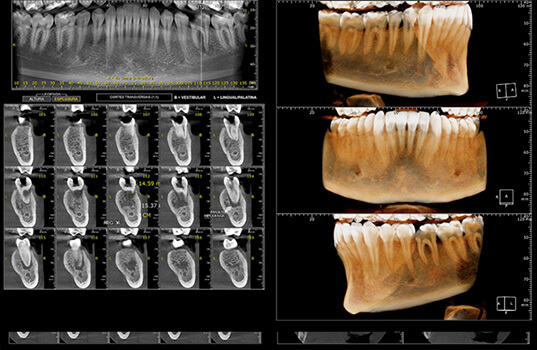

A Radiografia Panorâmica é uma radiografia de boca que fornece uma visão ampla dos dentes, mandíbula e maxila. É usada na odontologia para ajudar a identificar problemas dentários, como cáries, infecções, fraturas e outros problemas ósseos. Além disso, a Radiografia Panorâmica também pode ser usada para planejar tratamentos dentários, como a colocação de próteses e implantes dentários, como também para avaliar o desenvolvimento de tratamentos já realizados.

Na Radiografia Panorâmica, o paciente é posicionado na máquina de Raio-X e precisa ficar parado por alguns segundos enquanto a máquina faz a imagem. A imagem resultante mostra uma visão ampla da boca, mandíbula e maxila, permitindo aos dentistas visualizarem as estruturas ósseas e dentárias de uma só vez.